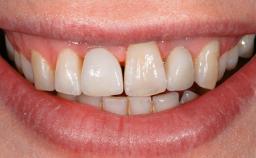

A 77-year-old male patient was referred for the management of frequent and repeated acrylic fracture of his existing mandibular fixed full-arch implant-supported metal/acrylic prosthesis. He also complained about softtissue soreness and the lack of retention and stability of his maxillary removable partial metal/acrylic prosthesis. Both prostheses had been delivered two years previously as part of his full-mouth rehabilitation (caries, tooth wear, tooth fracture). His medical history revealed high blood pressure, controlled with the use of antihypertensive medication.